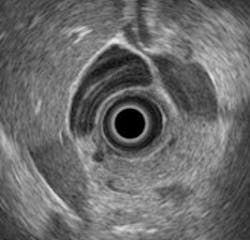

An assistant professor of physics at Kettering University (Flint, MI, USA) is seeking a better way to diagnose between chronic pancreatitis and pancreatic cancer by analyzing endoscopic ultrasound images.

Traditionally, doctors have mainly used the images from ultrasound systems in a qualitative way, looking at the shape, color, and pattern of the imaged organs to make their diagnosis.

Kumon and his collaborators, however, are working to quantitatively analyze the radio frequency data that underlies the ultrasound images to try to distinguish malignant from benign tissue states.

His studies to date show that a spectral analysis of the backscattered signals obtained by using electronic array echoendoscopes can provide a noninvasive method to quantitatively discriminate between chronic pancreatitis and pancreatic cancer.